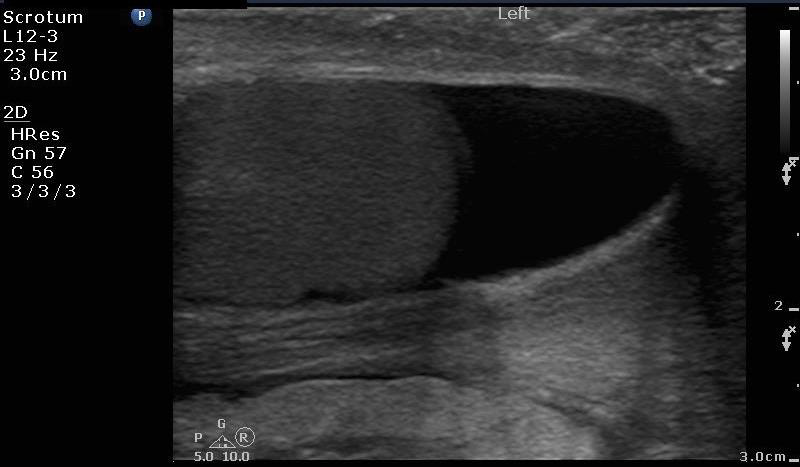

- Sonographically, a simple hydrocele is seen as an anechoic dark fluid collection surrounding the testicle. (Figure 4)

Figure 4. Image of the left testicle with hydrocele